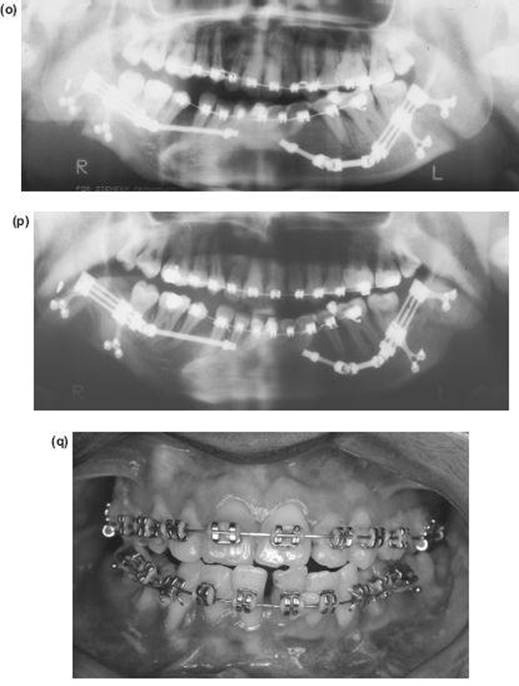

7. The nasal septum and pterygoid plates are separated intraorally, as in the Le Fort I operation.